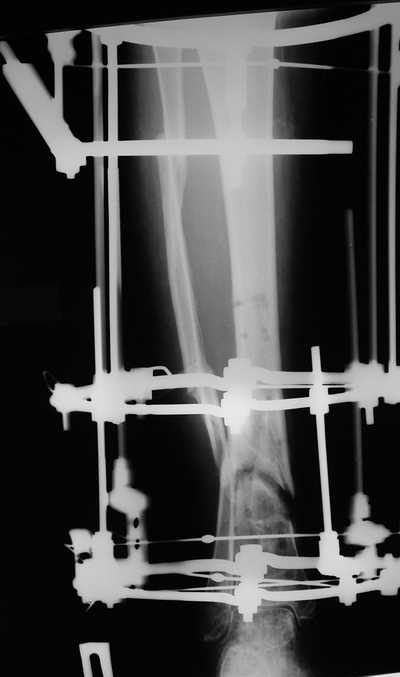

остеотомия м\б кости, аппарат Илизарова. По рентгенограммам в двух проекциях произведено планирование устранения смещений (рис 2 и 3), между вторым и третьим кольцом установлены 6 телескопических дистракторов Гесапода, данные введены в программу, и далее втечение 10 дней больная подкручивала телескопы согласно выданной компьютером инструкции. По завершению репозиции гексаподные телескопы обратно заменены на обычные штанги от аппарата Илизарова (рис 4 и 5). Еще через две недели забит гвоздь (рис 6, контроль

через 4 месяца).

Адаптация отломков гексаподом за 5 дней (рис 5). Замена гексапода на обычные штанги (рис 6 и 7)